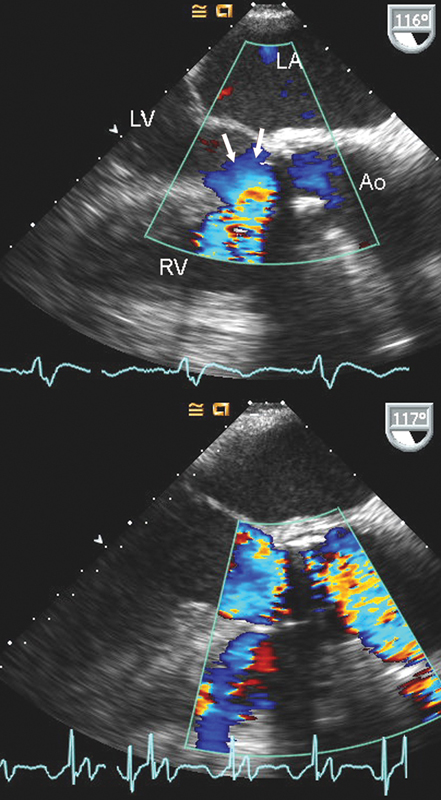

فحوصات تشخيصية لبعض امراض القلب والشرايين التاجية